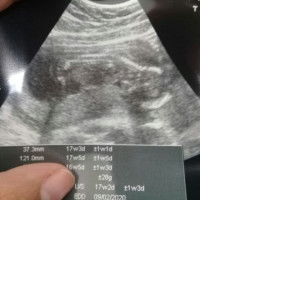

How many weeks pregnant were you when you found out you were pregnant?